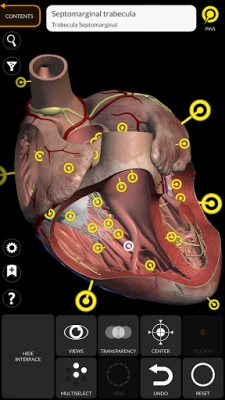

"Anatomy 3D Atlas" allows you to study human anatomy in an easy and interactive way.

Through a simple and intuitive interface it is possible to observe every anatomical structure from any angle.

The anatomical 3D models are particularly detailed and with textures up to 4k resolution.

The subdivision by regions and the predefined views facilitate the observation and the study of single parts or groups of systems and the relationships between different organs.

ANATOMICAL 3D MODELS

• Cardiovascular system

• Simple and intuitive interface

• Rotate and zoom each model in 3D space

• Option to hide or isolate single or multiple selected models

• Filter to hide or display each system

• Transparency function

• By selecting a model or a pin, the related anatomical term shows up

"Anatomy 3D Atlas" allows you to study human anatomy in an easy and interactive way.

Through a simple and intuitive interface it is possible to observe every anatomical structure from any angle.

The anatomical 3D models are particularly detailed and with textures up to 4k resolution.

The subdivision by regions and the predefined views facilitate the observation and the study of single parts or groups of systems and the relationships between different organs.

• Simple and intuitive interface

• Rotate and zoom each model in 3D space

• Option to hide or isolate single or multiple selected models

• Filter to hide or display each system

• Transparency function

• By selecting a model or a pin, the related anatomical term shows up